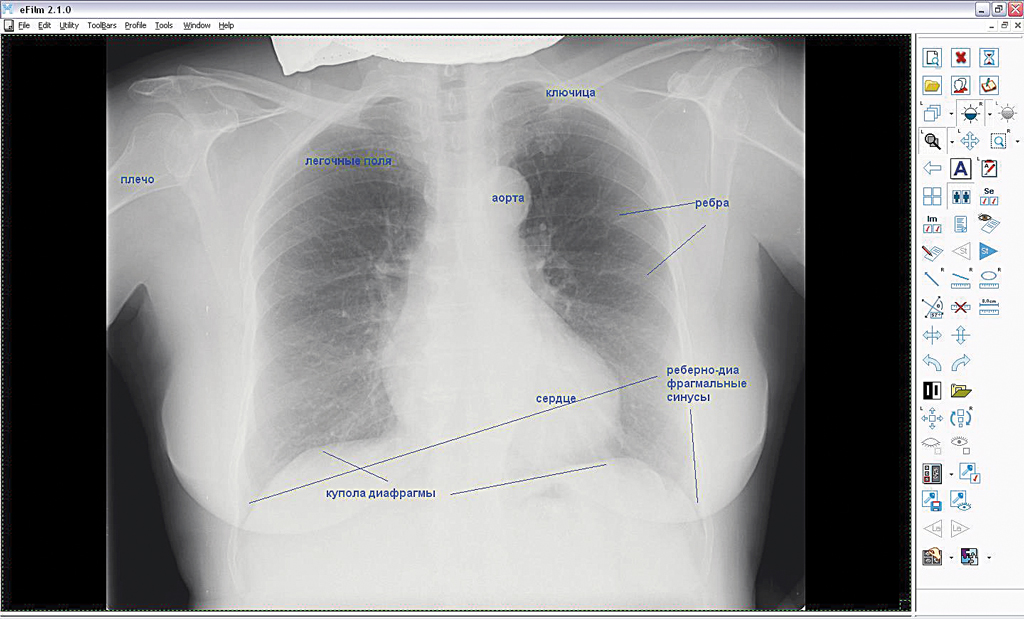

В программу ОМС планируют включить описание флюорографии грудной клетки с помощью искусственного интеллекта.

И теперь Федеральный фонд обязательного медицинского страхования и Минздрав России заняты оценкой возможности включить в базовую программу обязательного медицинского страхования описание флюорографии грудной клетки и компьютерной томографии головного мозга с использованием искусственного интеллекта.